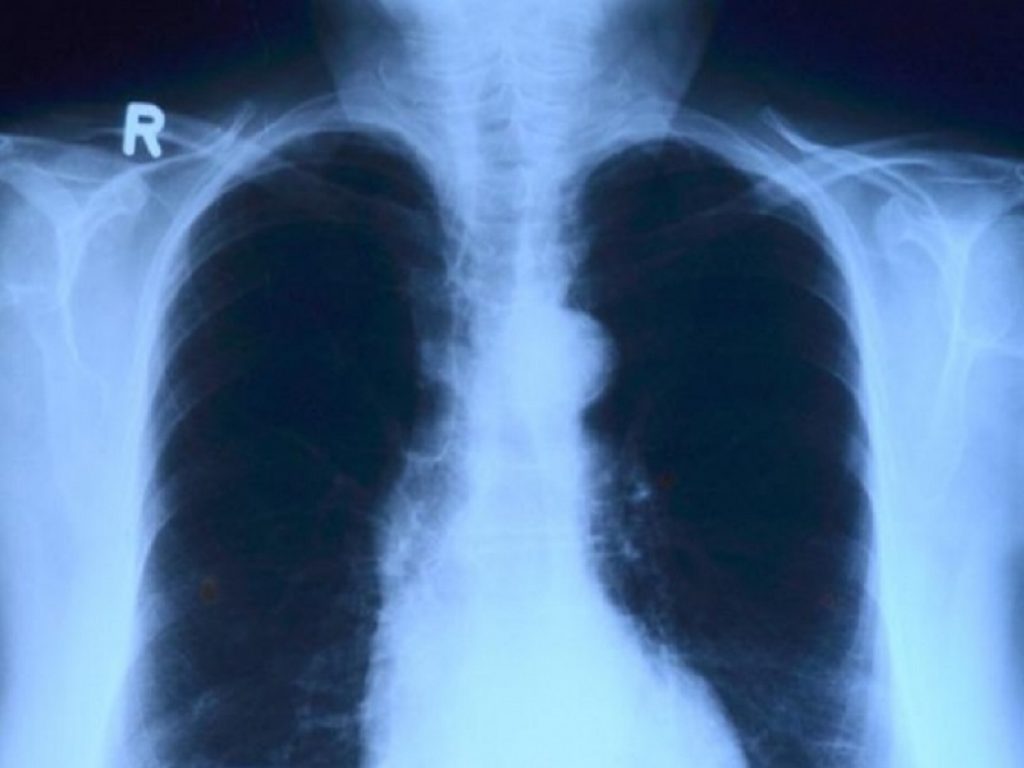

Le bronchiettasie rappresentano una condizione respiratoria cronica caratterizzata da infiammazione e infezioni, responsabili dell’ispessimento delle pareti bronchiali e ad episodi di riacutizzazione periodica.